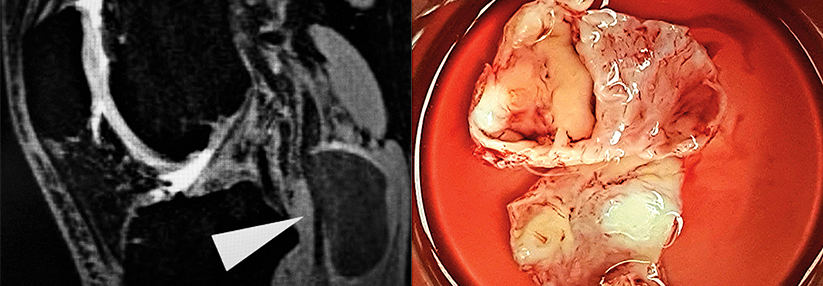

Da der Trend insgesamt Richtung endovaskulärer Aortenreparatur geht, sind die beobachteten Geschlechterunterschiede bei diesem Verfahren bedenklich, so die Autoren. Über die Ursachen der Differenzen könne man derzeit nur spekulieren. Möglicherweise existieren für Frauen einfach keine passenden Stentgrafts, da sich ihre Befunde anatomisch oft komplexer präsentieren – z.B. mit einem kürzeren und schmaleren Aneurysmahals.